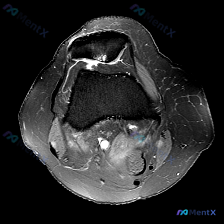

问了软骨异常,T1序列却啥都看不到?这个踝关节MRI病例太容易踩坑

最近碰到一个很有启发的病例,临床问题是问这张踝关节MRI-T1矢状位影像的观察结果是不是软骨异常,整理一下完整分析思路给大家。

本次仅提供踝关节MRI-T1序列-矢状位单张图像,先把客观阅片结果整理出来:

- 骨骼结构:胫骨远端、距骨、跟骨、足舟骨及部分楔骨显示清晰,骨皮质连续,骨髓腔内脂肪信号正常,无皮质中断或异常信号区

- 关节间隙与软骨:胫距关节间隙无明显狭窄增宽,关节软骨面轮廓可辨,未见明确剥脱或缺损

- 软组织与肌腱:跟腱走行正常,信号均匀边缘规整,无增粗或信号异常,未见明显腱鞘囊肿或严重软组织水肿

- 整体评估:未见明确病理性改变,无距骨穹窿骨软骨损伤、骨髓水肿、骨折线,无肌腱韧带撕裂、无明显关节积液征象